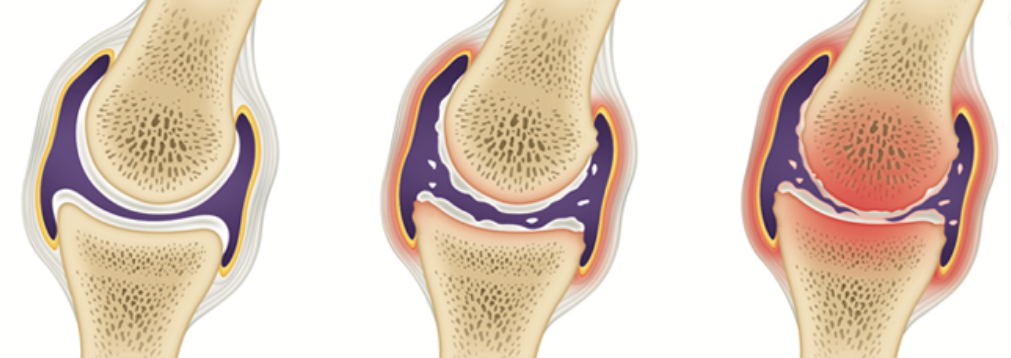

연골의 필수 성분인 글루코사민은 우리 몸에서 원래 스스로 생성되는 성분입니다. 그러나 나이가 들어 가면서 글루코사민 생성 능력은 현저히 감소하게 됩니다. 이에 따라 자연스럽게 관절연골의 완충 능력은 나빠지게 되고, 손상받기 쉬운 상태가 되어 버립니다. 그리고 이 손상이 염증을 유발합니다. 이것이 바로 관절염입니다.

줄어든 글루코사민 생성능력만큼 음식이나 영양제를 통해 글루코사민을 충분히 공급해주면면 연골의 파괴를 막을 수 있고, 연골 세포의 증식을 촉진시킬 수 있습니다. 그러므로, 적절한 글로코사민 섭취는 관절염 등 관절 질환을 앓고 있는 사람들에게 큰 도움을 줄 수 있습니다.